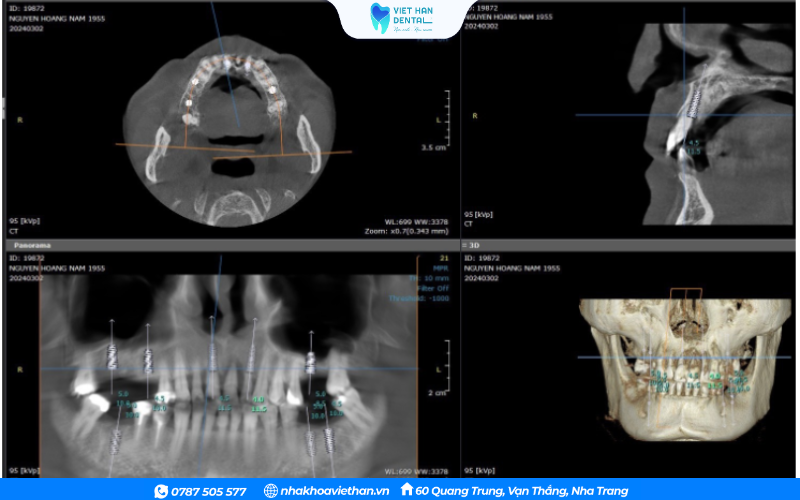

Trong buổi thăm khám đầu tiên tại Nha khoa Việt Hàn, bác sĩ Khổng Văn Quân trực tiếp kiểm tra, chụp phim CT Conebeam 3D và đánh giá toàn diện cấu trúc xương hàm – nướu – răng của chú Nam. Kết quả cho thấy tình trạng răng miệng của chú đã bước vào giai đoạn nặng và nhiều nguy cơ biến chứng nếu không được điều trị kịp thời.

Dựa trên kết quả phim CT 3D và tình trạng răng miệng thực tế, bác sĩ Khổng Văn Quân đã lên một kế hoạch điều trị rõ ràng, từng bước để vừa an toàn vừa đạt hiệu quả cao nhất cho chú Nam.